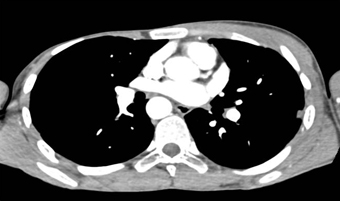

On this follow-up study for a vascular ring we also define

Polands syndrome

Loeys Dietz syndrome

Rasmussens Triad

Marfans syndrome